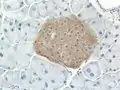

Mouse islet immunostained for pancreatic polypeptide

Mouse islet immunostained for pancreatic polypeptide Mouse islet immunostained for insulin

Mouse islet immunostained for insulin Mouse islet immunostained for glucagon

Mouse islet immunostained for glucagon